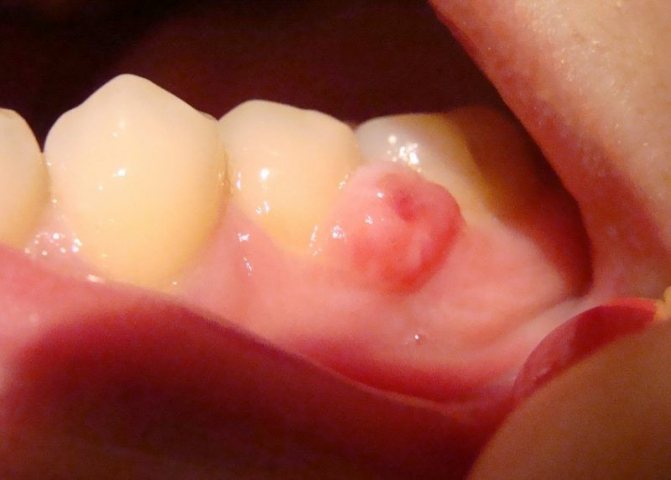

Фиброзный

Формируется из фиброзной десневой ткани с вложенными в нее костными поперечными включениями. Образуется только с вестибулярной стороны первых моляров или премоляров.

По цвету нарост совершенно неотличим от десны, при этом по форме бывает овальным или круглым с плотной консистенцией. Первоначально его поверхность ровная, но по мере его роста она обретает бугристость. Увеличиваясь, может через межзубные промежутки переходить на обратную сторону зубов.

Из всех видов разрастаний, фиброматозный имеет благоприятный прогноз лечения, растет медленно, не переходит в злокачественное состояние, безболезненный и не проявляет кровоточивости.

Гигантоклеточный

Образуется из остеогенных клеток и располагается всегда на альвеолярном гребне, закрывая постепенно собой коронки. Опухоль плотная, достаточно упругая, округлая, буро-коричневого цвета, растет медленно, но ее разрастания могут достигать объемов, нарушающих симметричность лица.

В единичных случаях проявляет болезненность, а при пальпации дает непродолжительное кровотечение. В зоне ее присутствия зубы расшатываются.